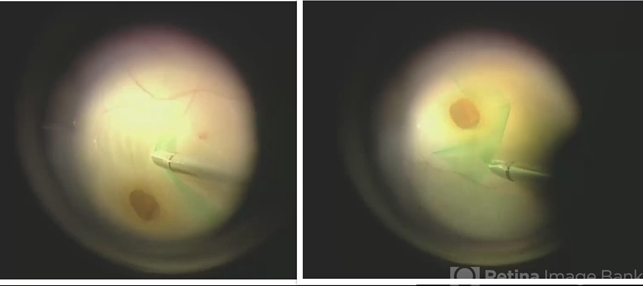

- macular hole

- ILM peeling for macular hole in setting of retinal detachment.